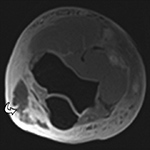

Truncation artifact is typically seen at tissue interfaces with an abrupt change in intensity of the MR signal and is also referred to as Gibbs phenomenon or ringing (Czervionke, 1988). This artifact occurs due to undersampling of the several phase-encoding steps of high spatial resolution and is manifested by dark or bright lines occurring parallel to the periphery of the region with abrupt signal intensity shift (Singh, 2014). Truncation artifact commonly occurs at fat-muscle and CSF-spinal cord interfaces and has been reported to simulate spinal cord syrinx or atrophy, intervertebral disc abnormalities, and meniscal tears (Figure 18) (Singh, 2014; Levy, 1988; Bronskill, 1988; Turner, 1991; Breger, 1988). Imaging with at least 192 phase-encodings steps, as well as a smaller FOV with increased matrix size along the phase-encoding direction, can reduce truncation artifacts (Peh, 2001). As with wraparound artifact, truncation may be reduced by switching the phase- and frequency-encoding directions.

Truncation Artifact. (A) Sagittal STIR MR image demonstrates T2 hyperintense line (arrowheads) within the anterior spinal cord due to spinal-cord CSF interface

Truncation Artifact. (B) Corresponding axial MEDIC (multi-echo data image combination) MR image demonstrates normal appearance of the spinal cord.